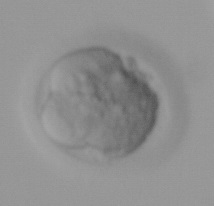

El siguiente estadío embrionario es el blastocisto: corresponde al día +5 y lo que podemos observar es la formación de una cavidad en el centro y un desplazamiento de las células hacia la periferia.

blastocisto